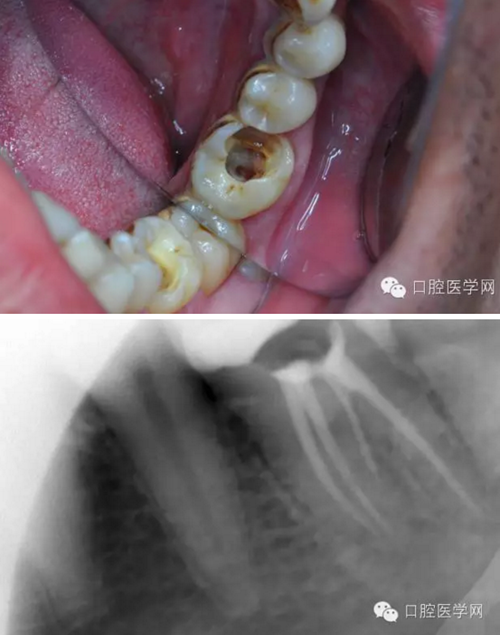

患者,肖某,男,32歲,#36慢性牙髓炎。遠中舌根根尖1/3彎曲而且鈣化不通,我用盡辦法疏通了很久也沒到達WL,(我一直在幻想,要是有超聲系統(tǒng)該多好,可是現(xiàn)實很骨感,我們單位暫時還沒有超聲系統(tǒng)),后來我放棄了,最后的根充片顯示遠中舌根充填物距根尖端2.84mm,屬于欠填范圍(根管內(nèi)充填物距根尖端2mm以上),其它三根根尖1/3鈣化相對沒那么嚴重,根充片顯示屬于恰填范圍(根管內(nèi)充填物距根尖端0.5~2mm)。歡迎網(wǎng)友們針對這個病例提出寶貴的建議!

9.png

10.png